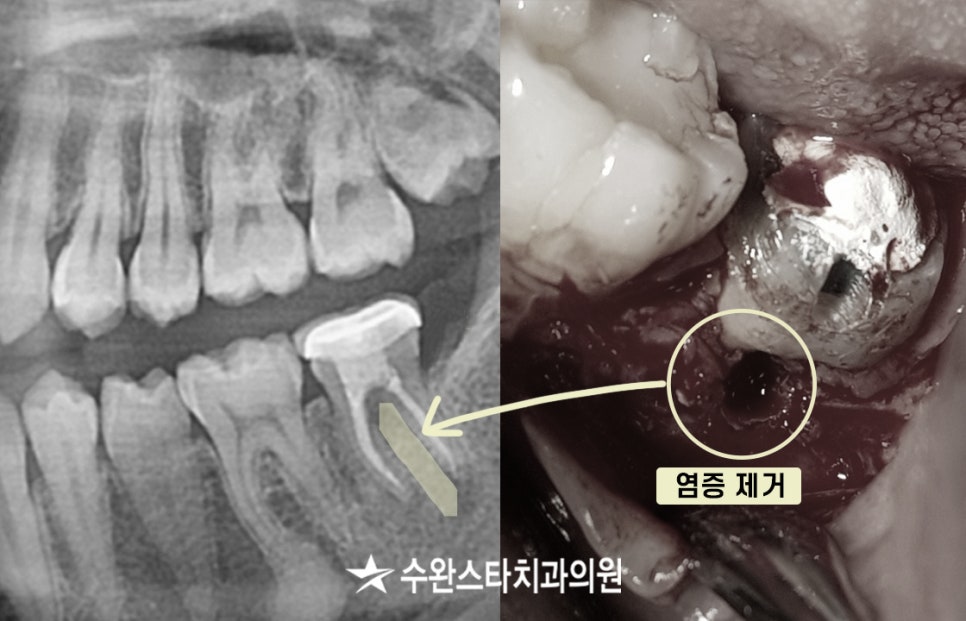

노란색으로 표시한 부분이

과거에 신경치료를

진행하셨던 치아입니다.

신경치료를 진행했던

부위가 세균에 의해 감염되어

뿌리 끝쪽에 염증이 생긴 것으로 보입니다.

뿌리 주변 염증, 20대 여성 (2023/11월 촬영)

뿌리 주변으로

염증이 생겨(노란색으로 표시)

뼈가 녹아서 까맣게 보이는 것입니다.

부패한 충전물을 제거하고

잇몸을 열어 뿌리 쪽으로 바로 들어가

염증을 제거하고 플라젠을 이용하여

세균을 사멸하고

치료를 마무리 지었습니다.